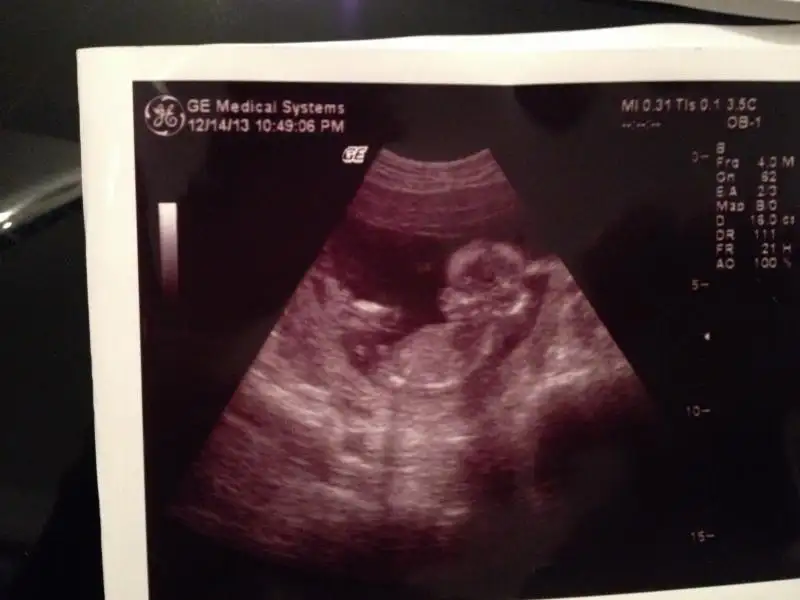

dr soylemeden siz gorun genital nub teorisi ( bebegin cinsiyeti)

Canim emin olmadiklarima demek istemiyrm ama sende pipi gibi gorunen bisi var ama o bacagida olabilir buyuk ihtimal kizsa eger nubu gorunmuyo

Teşekkürler yorumun için canım bende gördüm çıkıntıyı hatta yükleyemediğm fotolarda daha belirgin ama 13 haftalıkken bu kadar belirgin ve büyük pipi olurmu benim hala kızdan yana umudum var doktor bile erkeğe benziyor desede lütfen biraz daha yorum yazarmısın

zeynep 341 de yeni foto yükledim bunlara da bakar mısın yorum yapan arkadaşlar erkek dediler ama nedense hala kızdan yana umudum var yeşerip yeşerip duruyor gönlümden böyle geçtiği için mi acaba elbette her zaman hayırlısını diliyorum

bir daha bakıp yorumlar mısın lütfen